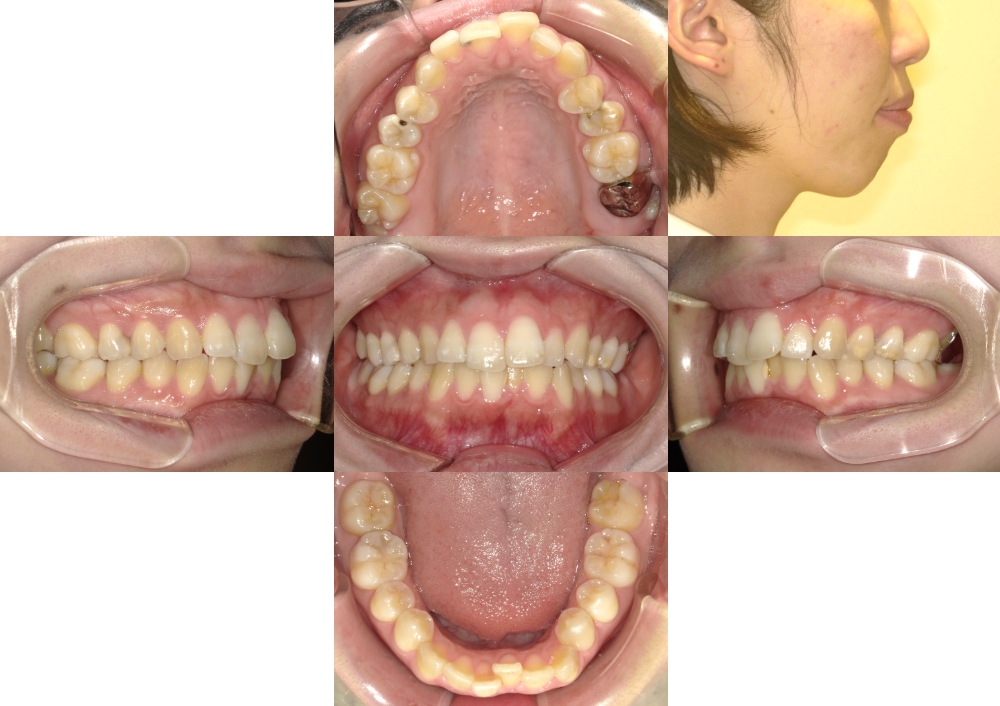

症例1

下顎前突

抜歯

ブラケット矯正

マウスピース矯正

(初診時)年齢

24歳

性別

女性

地域(住所)

日野市

主訴

受け口

診断

骨格性下顎前突、右上7番欠損

装置

マウスピース型矯正装置(インビザライン)、リンガルアーチ、マルチブラケット装置

抜歯/非抜歯

上顎両側8番、下顎両側4番抜歯(計4本)

期間

4年0カ月

費用

850,000円(税抜)(矯正装置・保定装置代込)

調整料 5,000円(税抜)×14回、 6,000円 (税抜)× 22回

症例写真

BEFORE

AFTER